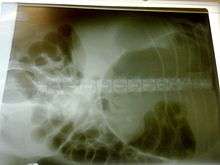

X-ray of a dog with bloat. Note the classic "double bubble" pattern indicating that stomach torsion has occurred in this case.

A diagnosis of gastric dilatation-volvulus is made by several factors. The breed and history will often give a significant suspicion of gastric dilatation-volvulus, and the physical exam will often reveal the telltale sign of a distended abdomen with abdominal tympany. Shock is diagnosed by the presence of pale mucous membranes with poor capillary refill, increased heart rate, and poor pulse quality. X-rays (usually taken after decompression of the stomach if the dog is unstable) will show a stomach distended with gas. The pylorus, which normally is ventral and to the right of the body of the stomach, will be cranial to the body of the stomach and left of the midline, often separated on the x-ray by soft tissue and giving the appearance of a separate gas filled pocket (double bubble sign).[17]